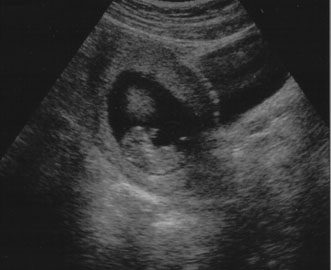

Maternal serum screening can identify pregnant women who are at an increased risk for having a baby with certain birth defects. Patient-specific risks for open spina bifida, Down syndrome and trisomy 18 (Edwards syndrome) (Fig. 1) can be determined by measuring the levels of certain proteins in maternal serum and combining those data with the patient's maternal age and clinical information.10 Women with a positive screen should be offered a definitive diagnostic test.

Fig. 1. Three-dimensional ultrasound showing typical pattern of trisomy 18. A clenched fist with the index finger overlapping the third and fourth fingers is distinctive of this disorder. Image courtesy of GE Medical Systems.